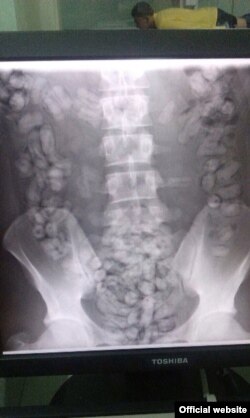

Рентген муҳожир қорнида 169 контейнер борлигини аниқлади

Аэропорт божхона хизмати ходимлари ўтказган рентген текшируви гумонланувчи ўзбек муҳожири қорнида жуда кўп кичкина контейнерлар борлигини аниқлади.

Россия Федерал божхона хизмати давлат инспектори Елена Грач Озодлик билан суҳбатда контейнерларда топилган модда героин экани ва унинг умумий оғирлиги 705,14 граммни ташкил этганини гапириб берди.

- Ҳа, у 19 сентябрь куни Домодедово аэропортида ушланди. Бир кун ўтиб – 20 сентябрь куни, Ўзбекистон фуқаросига нисбатан жиноий иш қўзғатилди. Унинг қорнидаги цилиндр шаклидаги контейнерлар қўлда ясалгани ва жами наркотик жойланган контейнерлар сони 169та экани маълум бўлди, деди Елена Грач.